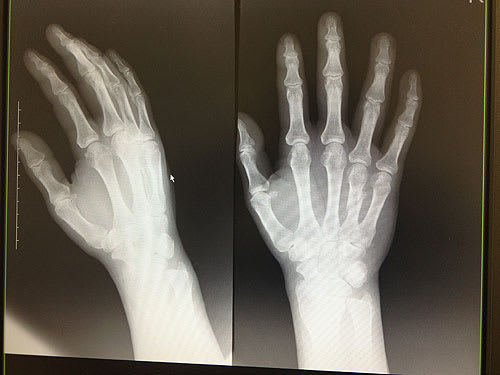

今日、3回目の診察。いよいよギプスが取れるだろうと期待して行った。とりあえずレントゲンを撮って経過を診てもらった。一応、骨は付いてきてるらしい。